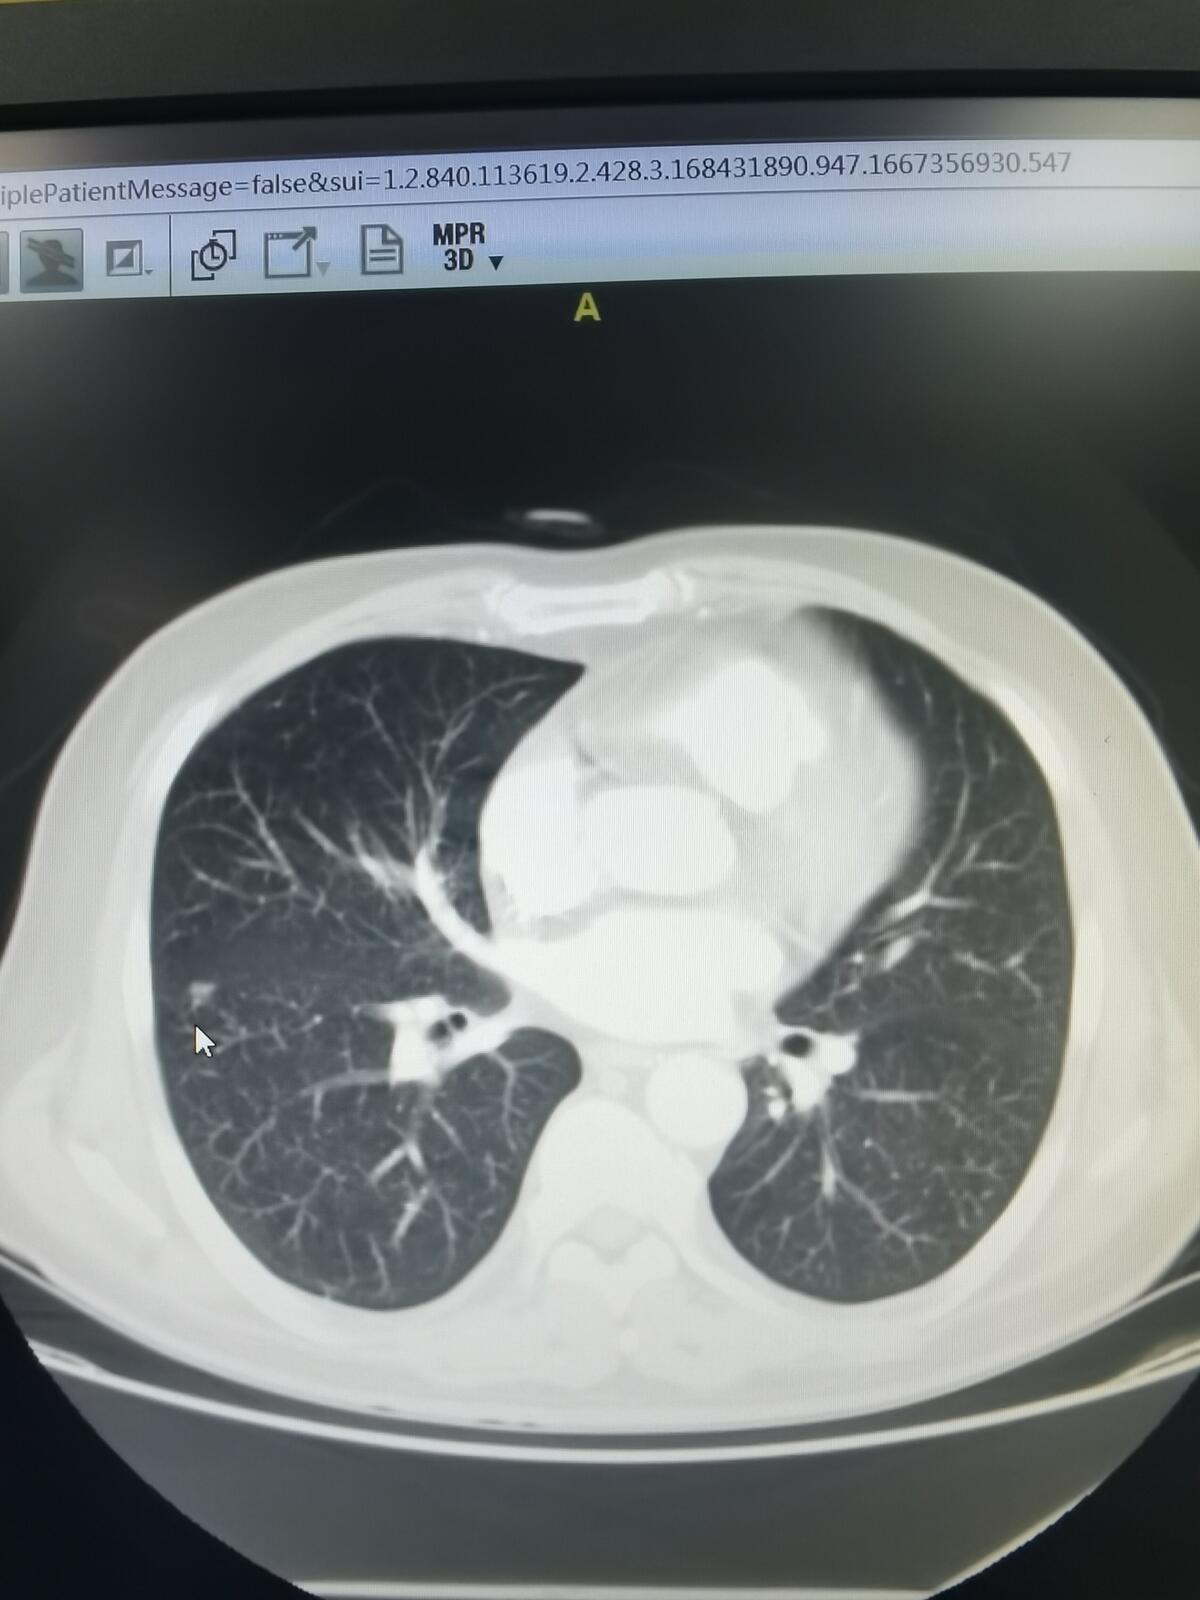

有一位60岁的男士前几天在我这里住院,他在当地医院做体检,发现了肺部有结节,找我做手术。他肺部就是多发的结节,比较大的有两个,一个在右上肺,是一个磨玻璃结节也就做GGO,报告里报的最大直径是15毫米,但是我测量,应该没有那么大。另外一个结节是在右肺下叶,是一个很小的,实性成分很多的结节,另外右肺还有一个特别小的磨玻璃结节。

右上肺那个磨玻璃结节,我觉得早期肺癌的可能性比较大,右下肺那个实性结节,我觉得良恶性均有可能。既然打算做手术,这两个结节可以一并切下来。手术后的病理显示,右上肺的GGO和右下肺的这个实性结节,都是微浸润肺腺癌,属于早期的肺癌。